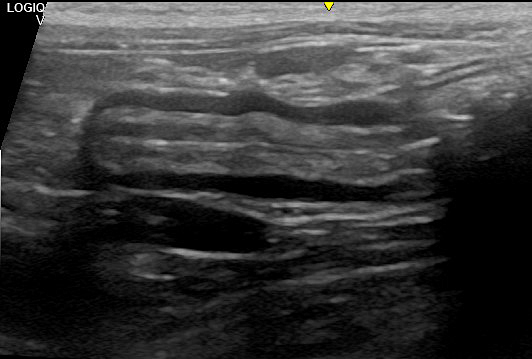

La ecografía abdominal reveló las siguientes alteraciones:

–Riñón izquierdo: presencia de masa en el polo caudal.

–Intestino: aumento de grosor de forma difusa afectando principalmente a capa muscular. Presencia de al menos dos zonas de engrosamiento severo (masas) con pérdida de estructura en capas.

-Ganglios: aumentados de tamaño e hipoecoicos.

-Hígado: hipoecoico con vesicula biliar con pared engrosada e hiperecogenica.